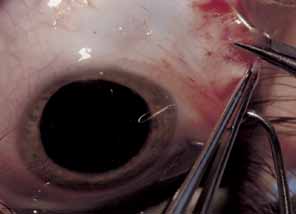

The muscle is then exposed; Tenon's capsule and the intramuscular septum are then dissected free (Figs. 1, 2, and 3). For a rectus muscle recession, a double-armed absorbable suture with a half circle needle is passed transversely through the muscle tendon, approximately 1 mm posterior to its insertion (Fig. 4 and 5). This suture is secured in place at both the superior and inferior poles of the muscle with locking bites. The muscle is disinserted from the globe.